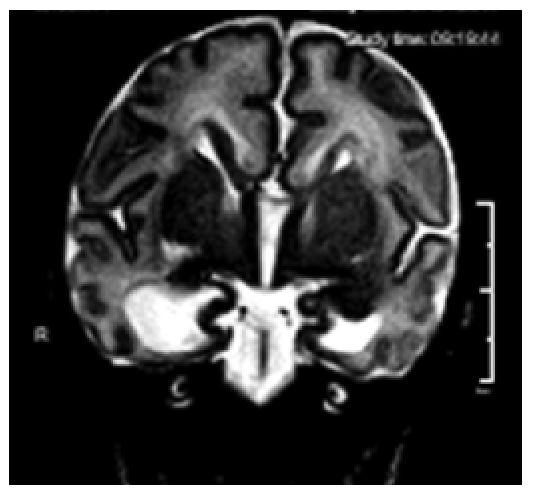

Рис. 4. Уменьшение объемов гиппокампов при заместительном расширении желудочковой системы головного мозга